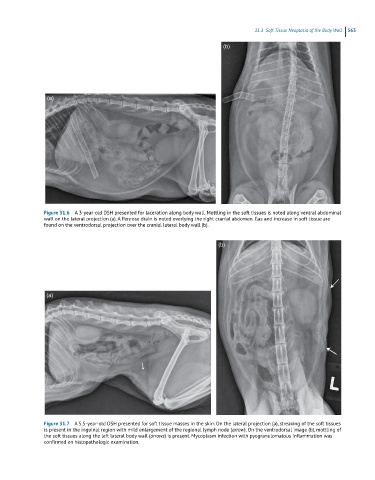

Figure 31.6 A 3-year-old DSH presented for laceration along body wall. Mottling in the soft tissues is noted along ventral abdominal

wall on the lateral projection (a). A Penrose drain is noted overlying the right cranial abdomen. Gas and increase in soft tissue are

found on the ventrodorsal projection over the cranial lateral body wall (b).

Figure 31.7 A 5.5-year-old DSH presented for soft tissue masses in the skin. On the lateral projection (a), streaking of the soft tissues

is present in the inguinal region with mild enlargement of the regional lymph node (arrow). On the ventrodorsal image (b), mottling of

the soft tissues along the left lateral body wall (arrows) is present. Mycoplasm infection with pyogranulomatous inflammation was

confirmed on histopathologic examination.